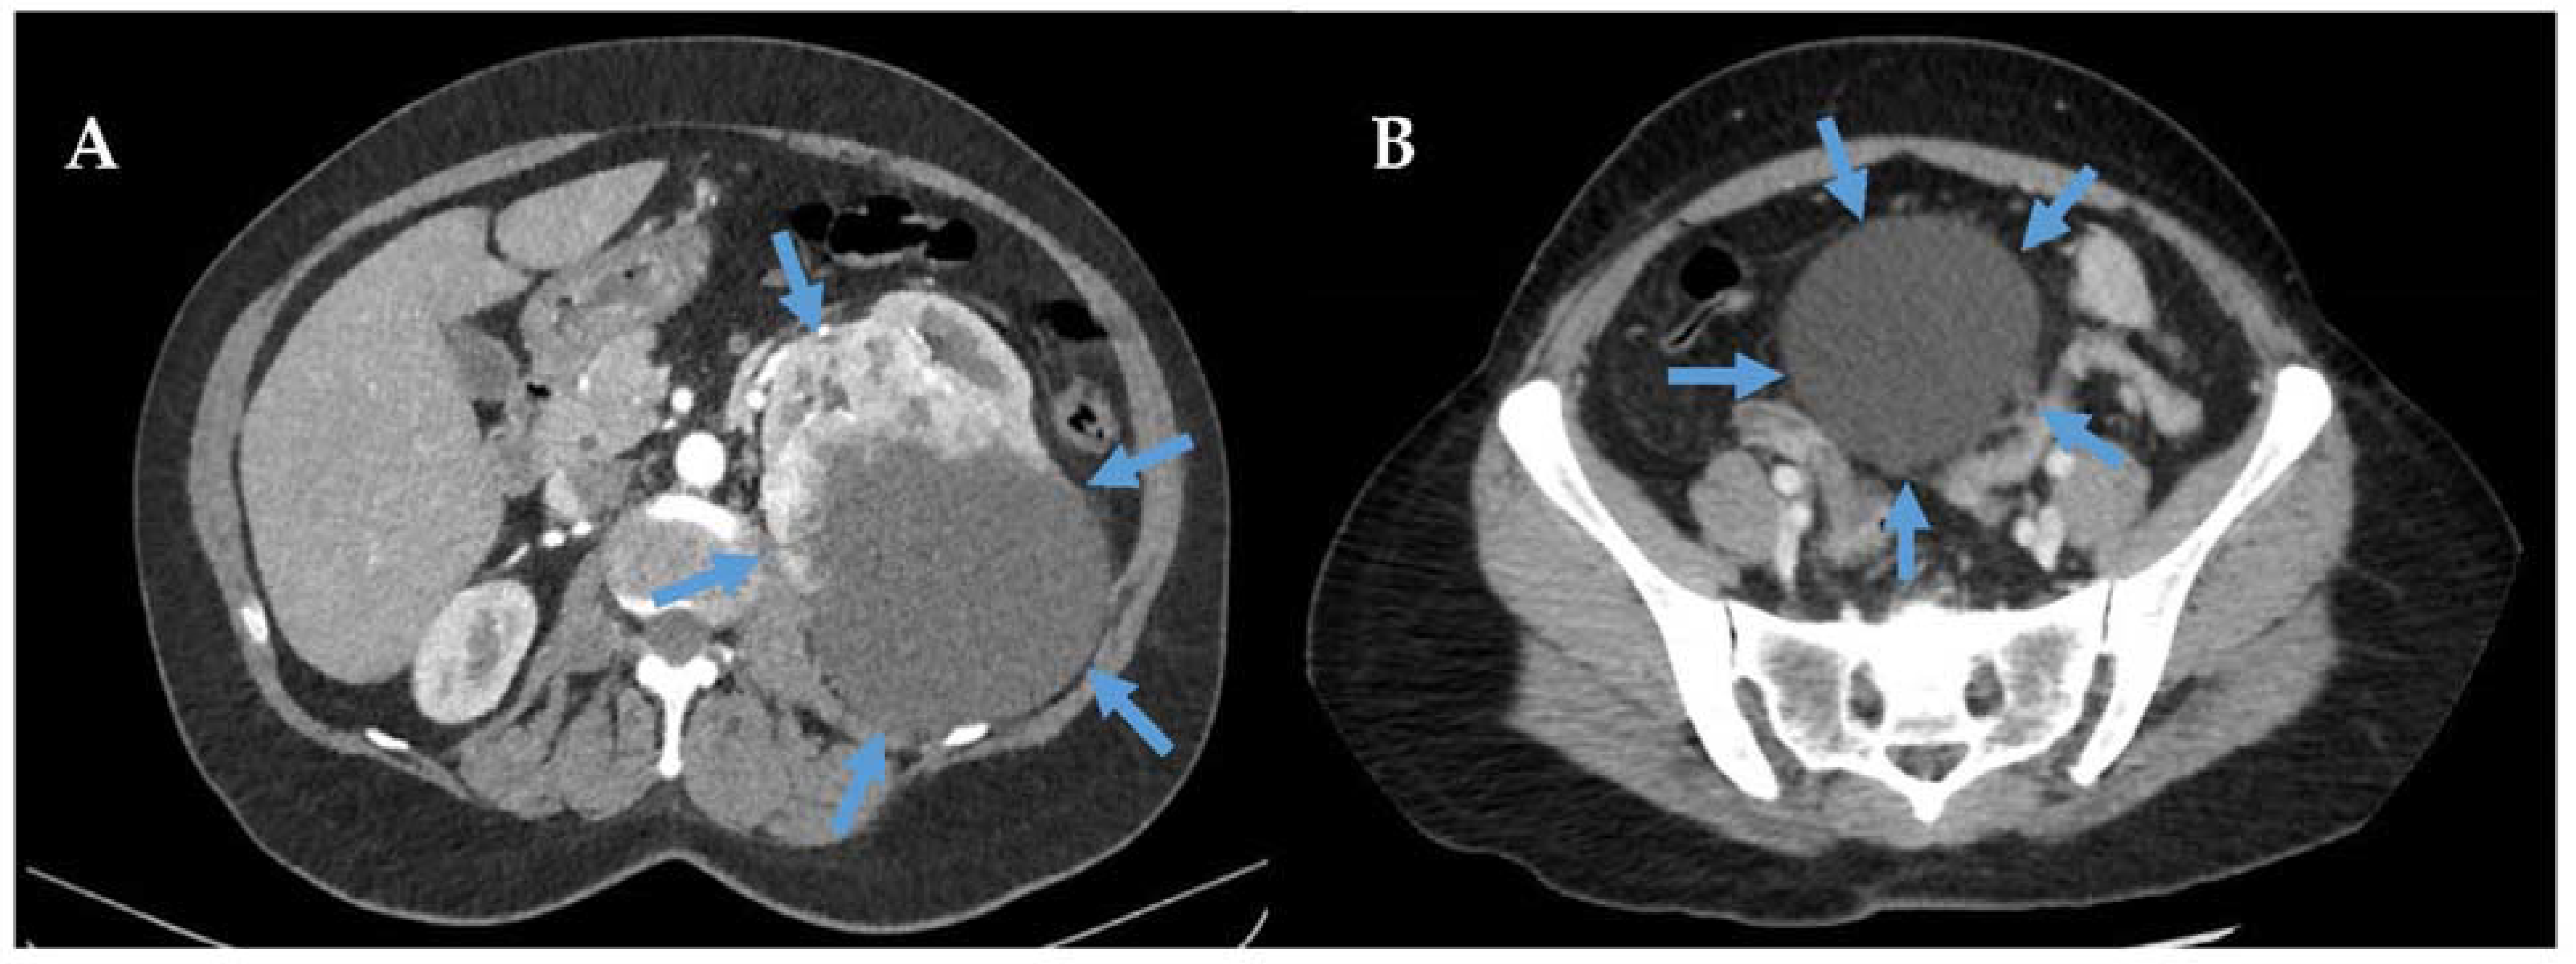

34-year-old Woman With Retroperitoneal Rhabdomyosarcoma.... | Download

www.researchgate.net

www.researchgate.net

retroperitoneal rhabdomyosarcoma axial contrast

34-year-old Woman With Retroperitoneal Rhabdomyosarcoma.... | Download

www.researchgate.net

www.researchgate.net

retroperitoneal rhabdomyosarcoma year contrast axial demonstrates bilateral extention